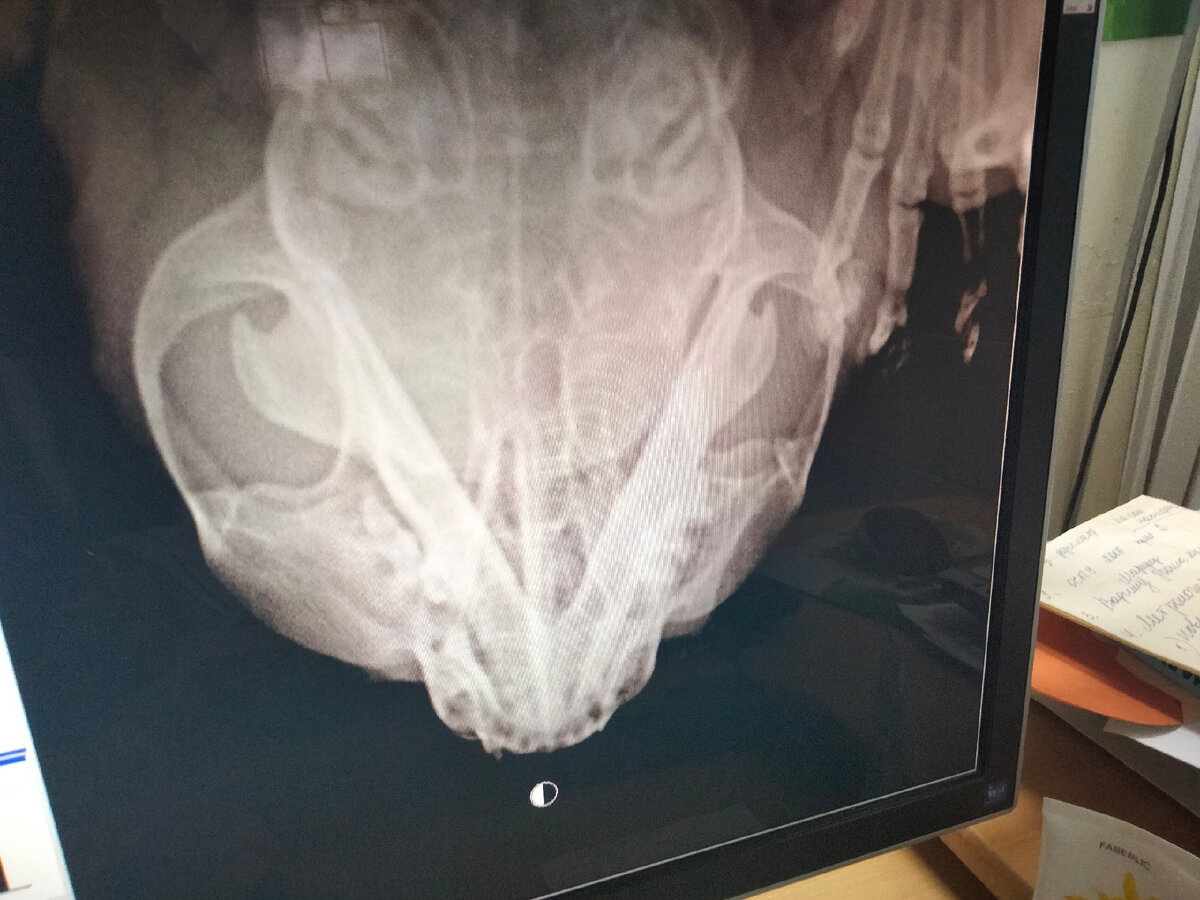

Персику снова сделали рентген, назначили лечение и боится волонтёр, что это ещё не конец. Зубы пока хорошие, их удалять врач отказался, а вот в лунках идёт воспалительный процесс из-за которого котик не может кушать.